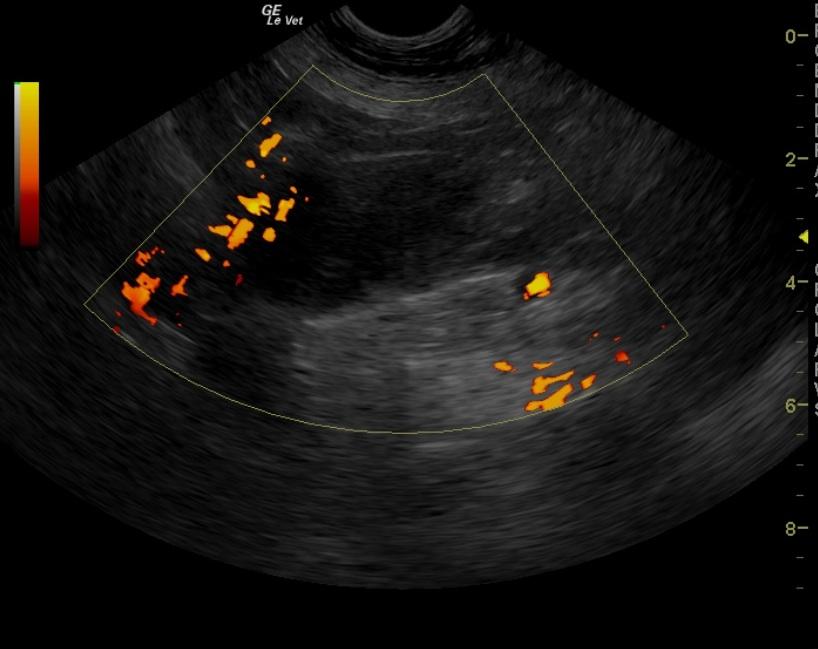

A 10-year-old FS Bull Mastiff dog with a history of urinary tract infections was presented for vomiting, polyuria/polydypsia, and pollakiuria. The urine appeared turbid, and analysis revealed isosthenuria, proteinuria, pyuria, and hematuria. Urine culture yielded E.coli. Abnormalities on CBC and serum biochemistry were monocytosis, mildly elevated ALP activity, and elevated lipase.